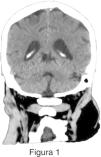

Figura 1 Paciente de 81 años sin antecedentes relevantes consultó al servicio de guardia por vértigo de inicio súbito. La tomografía computada (TC) de encéfalo sin contraste en plano coronal evidenció una dilatación ventricular con ensanchamiento de los surcos, las cisternas y el cuarto ventrículo.